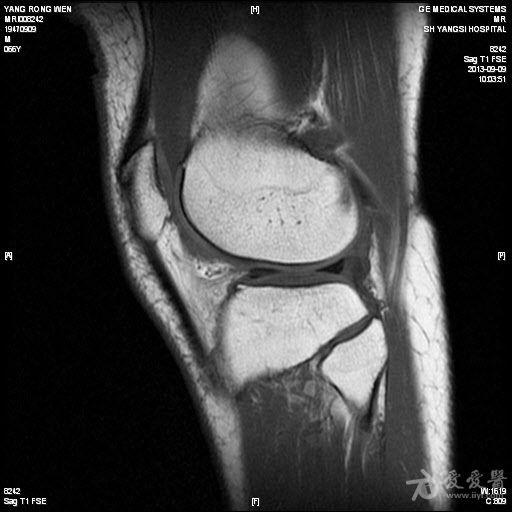

╯0╰ 儿童膝关节滑膜炎病因及治疗方法大揭秘!住院周期短等明显优势,在某些疾患中己逐步取代传统开放手术的趋势。 得益于关节镜技术在成人群体中的推广及发展,医护工作者对儿童膝关... 对各种不同类型的滑膜炎的显影无明显特异性。此外,MRI检查价格昂贵。 儿童膝关节滑膜治疗 药物治疗 目前治疗膝关节滑膜炎尚无特效药物...